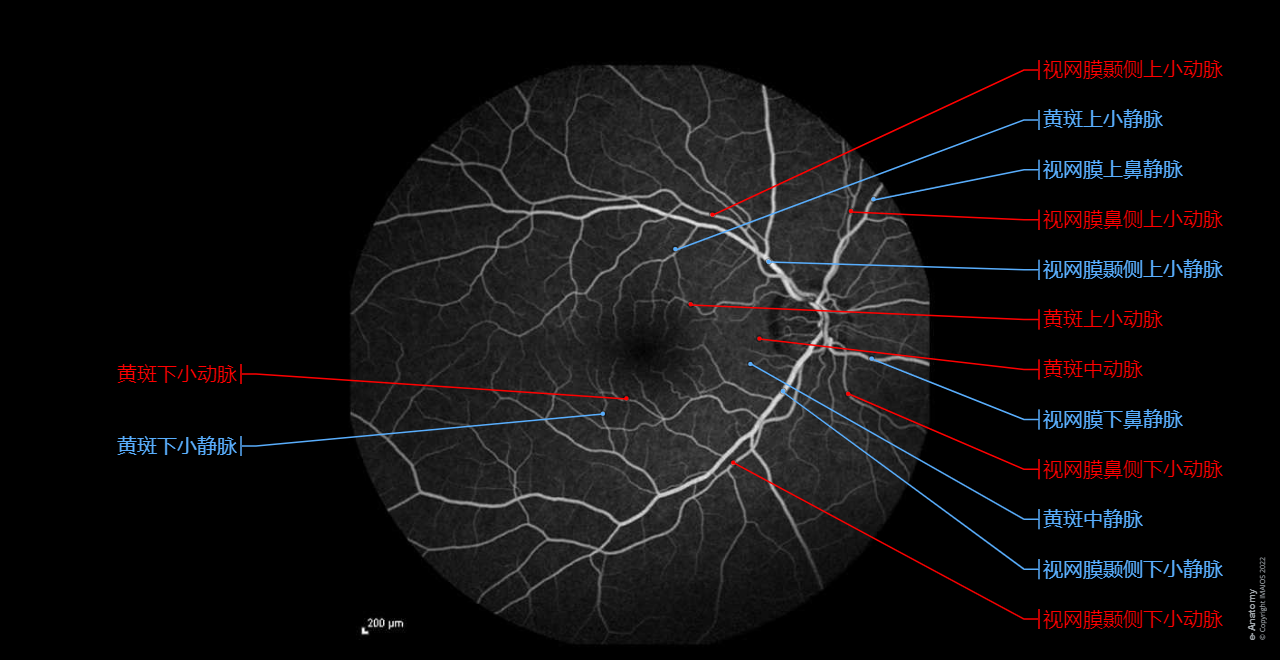

眼底荧光血管造影